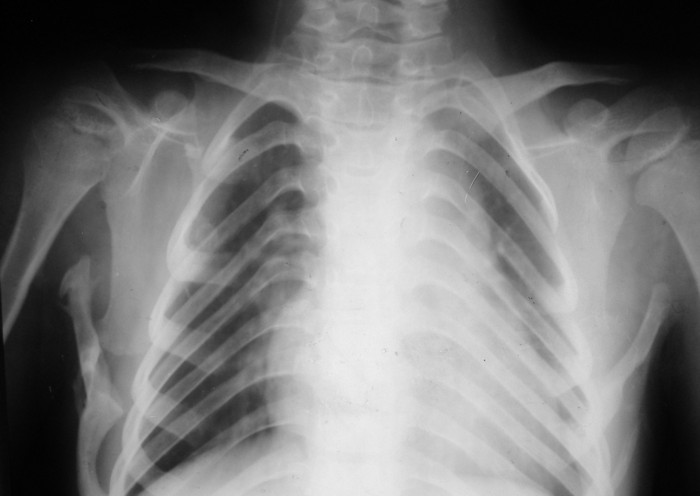

Жалобы: на нарушение функции верхних конечностей: невозможность движения в обеих правых плечевых и локтевых суставах; ограничение движений в шейном отделе позвоночника, наличие опухолевидных множественных образований на спине и пробам бедре.

Диагноз: врожденная аномалия развития шейного отдела позвоночника с резким нарушением функции в плечевых и локтевых суставах, множественных костно-хрящевые экзостозы, оссифицирующий миозит.

При инструментальном обследовании выявлено рестриктивный тип нарушения функции легких (крайне резкое снижение), обструктивный тип нарушения функции легких на уровне крупных бронхов (весьма значительное снижение).

рентгенограммы

это fibrodysplasia ossificans progressiva, генетически обусловленная прогрессирующая метаплазия соединительной и мышечной ткани в костную. Лечится (вернее, тормозится) консервативно, после попыток оперативного лечения и после травм - прогрессирует.